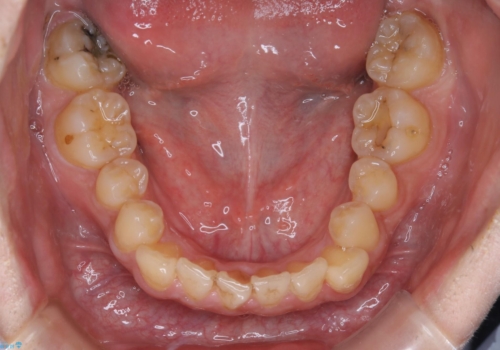

人生で初めてのクリーニングということもあり、プラークや歯石が大量に付いていました。それにより、歯茎の腫れもあり出血も多かったです。これから矯正をスタートしていくため、歯ブラシ指導を行いホームケアを頑張ってもらっています。